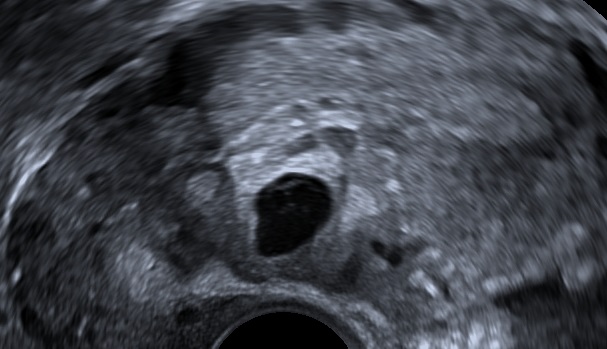

Visualize the ectopic pregnancy.